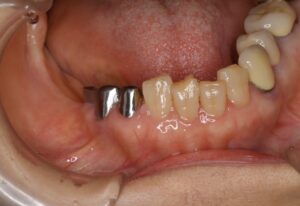

ケース1:右下奥歯3本を失った70代女性

当初は保険のクラスプ義歯を入れていましたが、動いて痛く、しっかり噛めないという訴えがありました。インプラントは希望されなかったため、テレスコープ義歯に変更。結果として右側でも硬いものが噛めるようになりました。写真の左は外したところ、右は装着したところです。手前2本の歯に内冠を作り、セメントでかぶせてあります。

この内冠に合わせて外冠が作られ、外冠の内面にはPEEK(ポリエーテルエーテルケトン)という耐久性の高い樹脂が貼られています。これが維持装置として働きます。